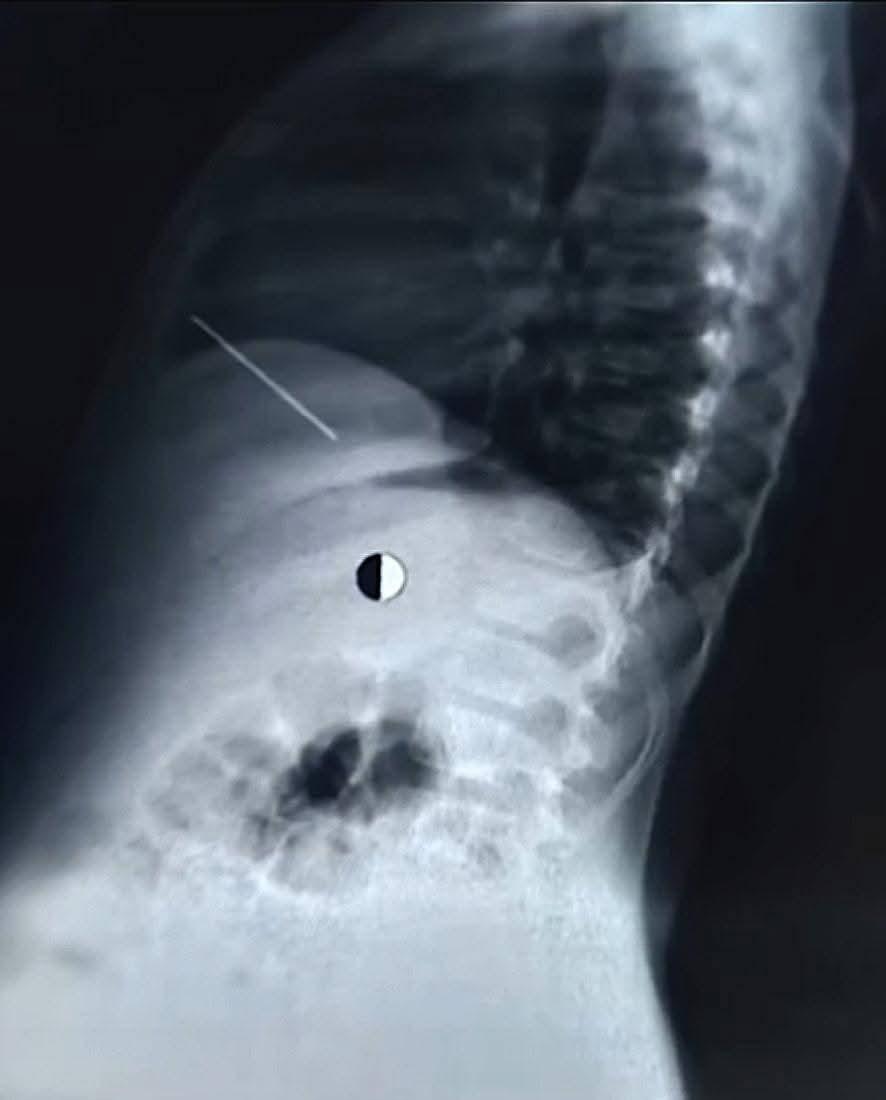

شهدت مستشفيات جامعة القاهرة (قصر العيني) إنجازاً طبياً جديداً يعكس كفاءة وتفوق "قلعة الطب" في التعامل مع الحالات النادرة والمستعصية، حيث نجح فريق طبي متخصص من قسم جراحة القلب والصدر في إنقاذ حياة طفل يبلغ من العمر 11 عاماً، حضر إلى المستشفى في حالة حرجة إثر اختراق مسمار "منجد" يبلغ طوله 5 سم لصدره واستقراره مباشرة داخل عضلة القلب، في واقعة طبية حبست الأنفاس وانتهت بانتصار جراحي مصري خالص.

بدأت تفاصيل الواقعة أثناء لهو الطفل مع أحد أصدقائه بمسدس مسامير، مما أدى إلى اندفاع المسمار ليخترق القفص الصدري ويستقر في القلب، وفور وصوله إلى مستشفى الاستقبال والطوارئ 185 برئاسة الأستاذ الدكتور أحمد ماهر مدير المستشفى، تم تفعيل بروتوكول التعامل العاجل مع الحالات الحرجة، حيث أشار الدكتور أحمد ماهر إلى أن سرعة دخول الطفل وتنسيق استدعاء جراحي القلب والصدر فور وصول الحالة كانا بمثابة حجر الزاوية في إنقاذ حياته، مؤكداً أن جاهزية غرف العمليات والطواقم الجراحية بالمستشفى تسمح بالتعامل مع مثل هذه الحوادث الجسيمة في دقائق معدودة.

وعلى الفور، تولى الفريق الجراحي بقيادة الأستاذ الدكتور حسام فتحي علي، رئيس وحدة حوادث جراحة القلب والصدر، إجراء عملية استكشاف عاجلة للصدر، حيث تبين وجود تهتك بالرئة اليمنى واختراق المسمار للغشاء التموري وإصابة القلب إصابة مباشرة تسببت في نزيف داخلي حاد حوله، وبمهارة فائقة تم استخراج المسمار وإصلاح التهتكات والسيطرة على النزيف بالكامل.